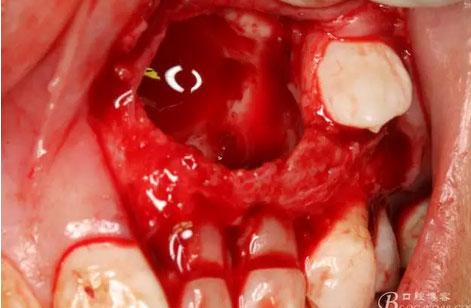

圖18.摘除囊腫后遺留的巨大骨腔

圖19.生理鹽水沖洗骨腔,修整骨腔表面

圖22.為了保留兩顆乳牙,不再去除遺留部分鈣化物,遂膠原蛋白海綿填塞兩個缺損骨腔。